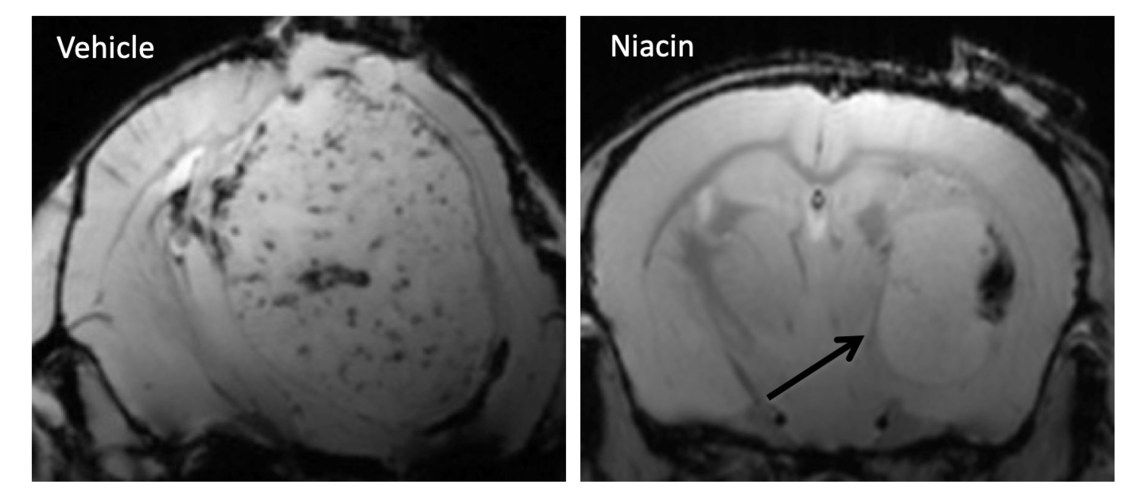

Mice (C57BL/6) were implanted with brain tumour-initiating cells (BTIC) and treated with niacin 7 days post-implantation. Tumor growth was monitored using MRI around day 49 to determine the therapeutic efficacy of niacin.

Glioblastoma (GBM) is an incurable brain cancer. A major reason for the dismal prognosis is the existence of brain tumor-initiating cells (BTICs), which are self-renewing chemo- and radio-resistant cancer stem cells that lead to tumor recurrence and progression despite treatment. We discovered that the immune defense cells of the CNS, microglia, and their circulating counterparts, monocytes (which become macrophages in tissues), are highly effective at reducing BTIC growth in culture but that this competency is lost in monocytes, macrophages and microglia (collectively referred to as myeloid cells) from GBM patients. My research project screened a library of 1,040 medications and discovered a compound that promotes myeloid cells activity to reduce BTIC growth in culture: niacin (vitamin B3). In mice with intracranial syngeneic or patient-derived BTICs, niacin elevates myeloid cells in brain tumor, reduces tumor volume on MRI and histology, and significantly prolongs survival of tumor-bearing mice. My current research work attempts to investigate the mechanisms and determinants of niacin in suppressing BTIC growth and test the overarching hypothesis that the compromised myeloid cells in patients with GBM can be reinvigorated by niacin to control the tumorigenecity of BTICs. I seek to mobilize the normally protective immunity to improve the prognosis of GBM. To translate the laboratory data to the clinic, a multi-disciplinary proposal that spans the laboratory to a Phase 1/2 clinical trial has been proposed.